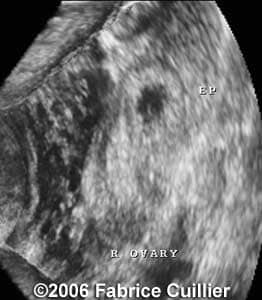

Case 2

case16a

case2a